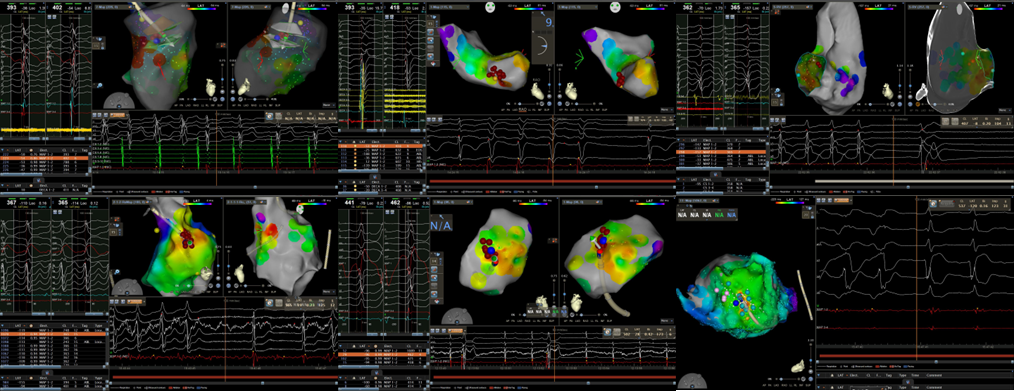

心血管内一科起搏电生理团队在面临急诊手术高风险及高不确定因素情况下,应用急诊射频消融方式顺利终止上述患者无休止室速,改善患者血流动力学及心脏功能。

传统认知中,射频消融术只能择期进行,并且仅适用于血流动力学稳定的患者。目前,在成熟完备的标测技术和手段加持下,对血流动力学不稳定的无休止室速行急诊射频消融术能转服窦律,为后续原发疾病诊治或ICD(体内除颤器)植入争取机会。